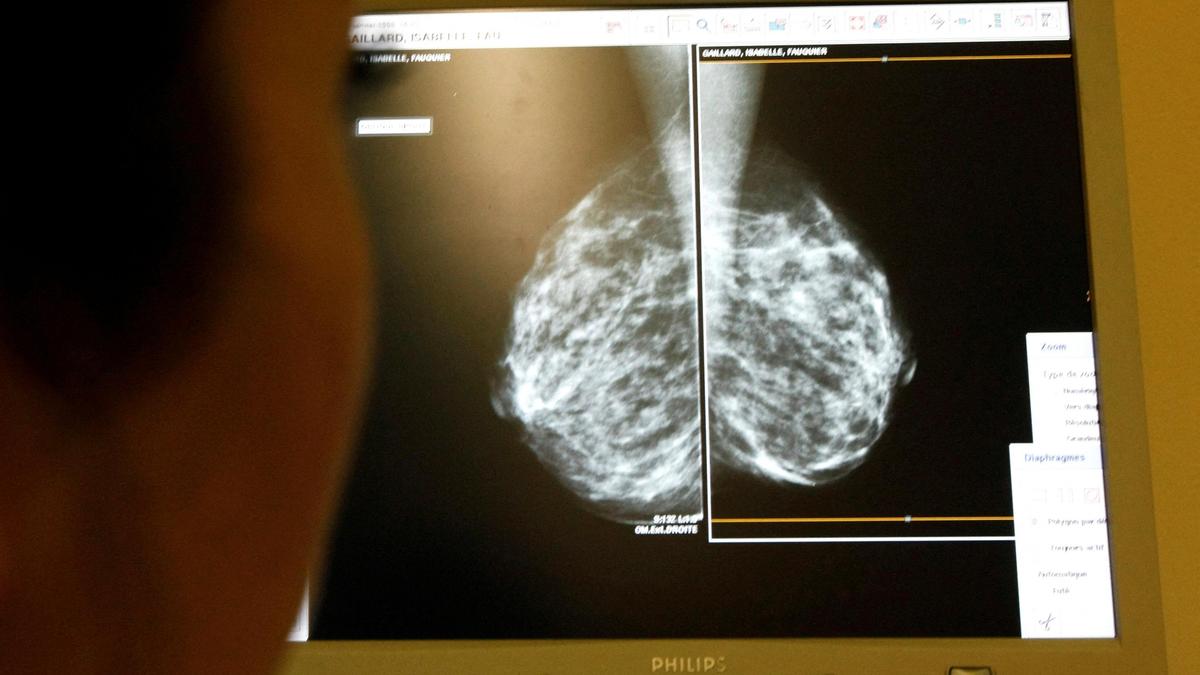

Study demonstrates that metastatic presentation in India is strongly influenced by tumour size, grade, nodal involvement, and lympho-vascular invasion, with health system context modulating the risk